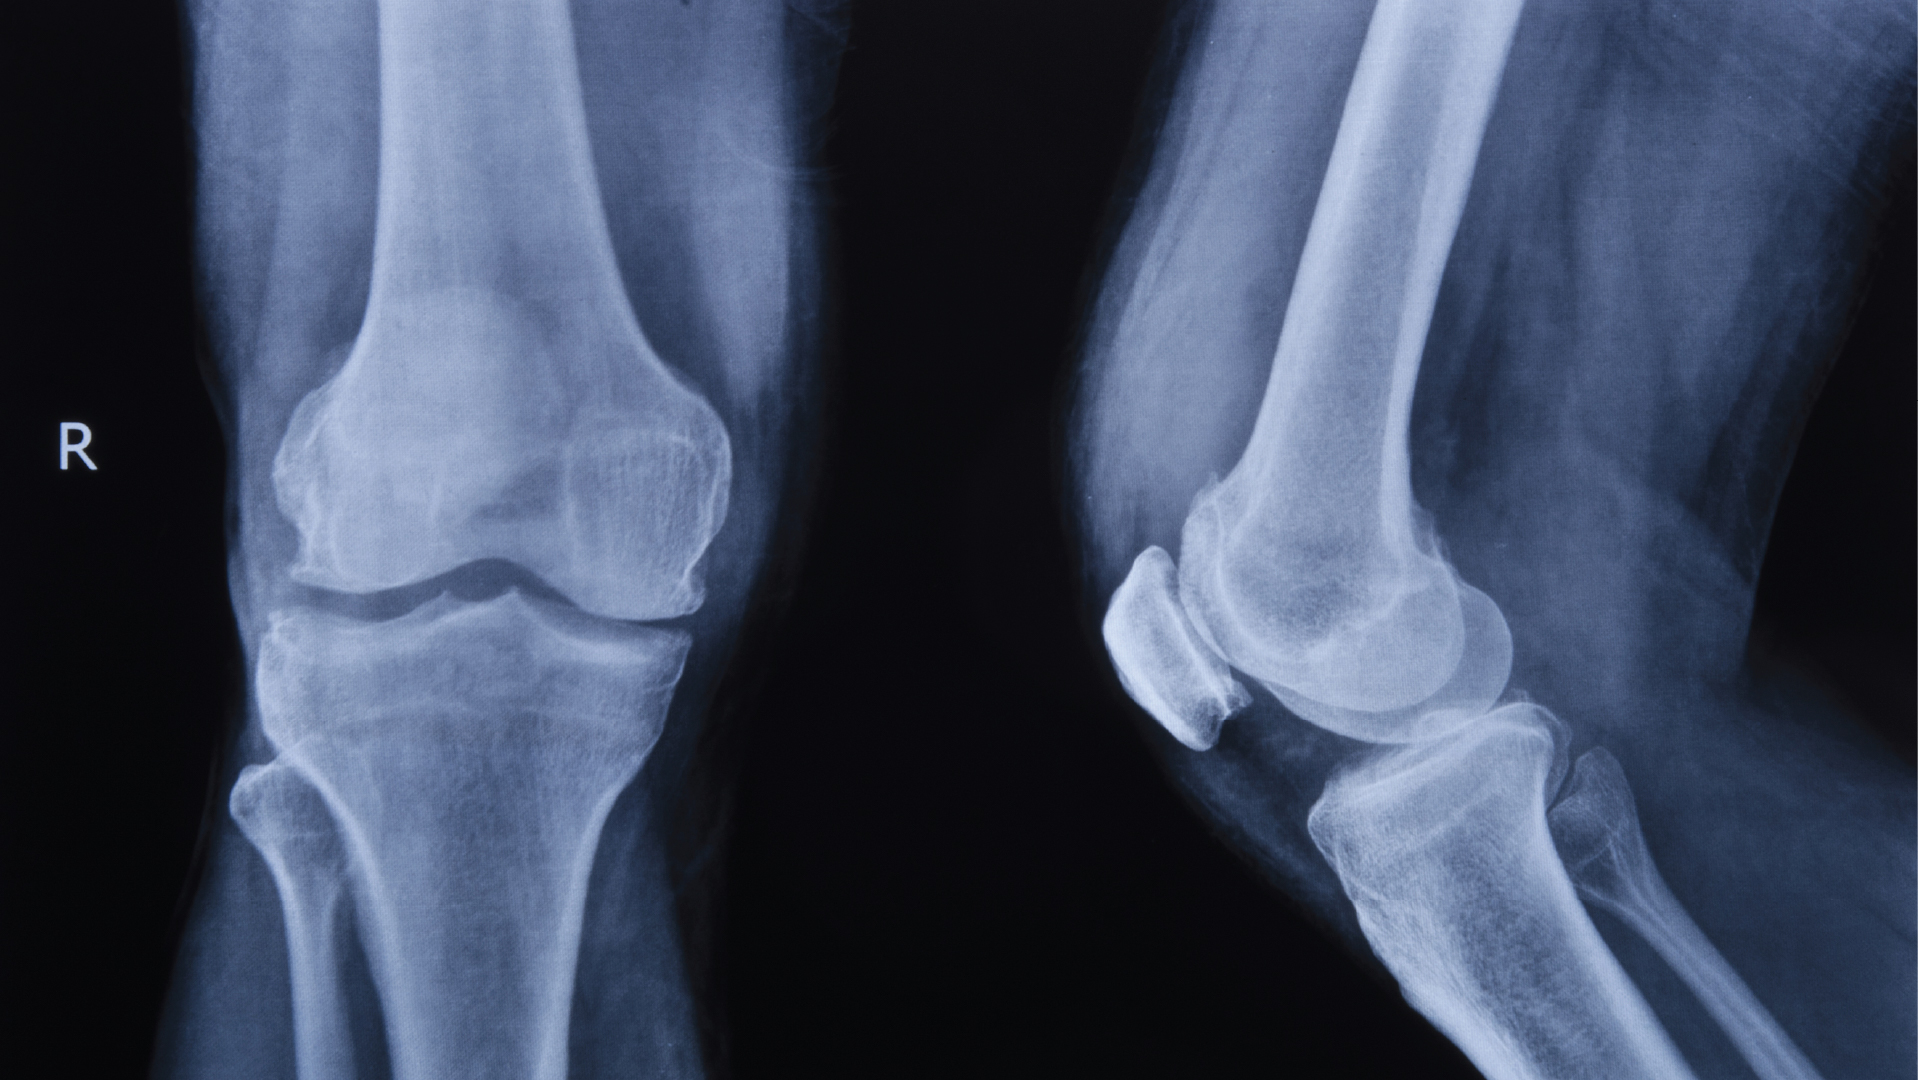

รศ.พล.อ.ท.นพ.จำรูญเกียรติ ลีลเศรษฐพร แพทย์เฉพาะทางกระดูกและข้อ จากโรงพยาบาลเอส เฉพาะทางกระดูกสันหลังและข้อ (S Spine and Joint Hospital)อธิบายว่า ข้อเข่าเป็นข้อต่อขนาดใหญ่ที่ต้องรับน้ำหนักของร่างกายตลอดเวลา ภายในข้อเข่าประกอบด้วยกระดูกอ่อน เอ็น กล้ามเนื้อ และกระดูกชิ้นสำคัญที่เรียกว่า “ลูกสะบ้า” (Patella) ซึ่งอยู่ด้านหน้าของข้อเข่า มีหน้าที่ช่วยเพิ่มแรงให้กล้ามเนื้อหน้าขาในการเหยียดเข่า และช่วยให้การเคลื่อนไหวของข้อเข่าเป็นไปอย่างราบรื่น

เมื่อเกิดภาวะข้อเข่าเสื่อม กระดูกอ่อนที่ทำหน้าที่รองรับแรงกระแทกจะค่อย ๆ สึกหรอ โดยเฉพาะบริเวณใต้ลูกสะบ้าที่ต้องรับแรงกดและแรงเสียดสีสูง ส่งผลให้เกิดอาการปวดเข่าด้านหน้า มักปวดชัดเจนเวลาขึ้นลงบันได ลุกนั่ง หรือใช้งานข้อเข่าเป็นเวลานาน